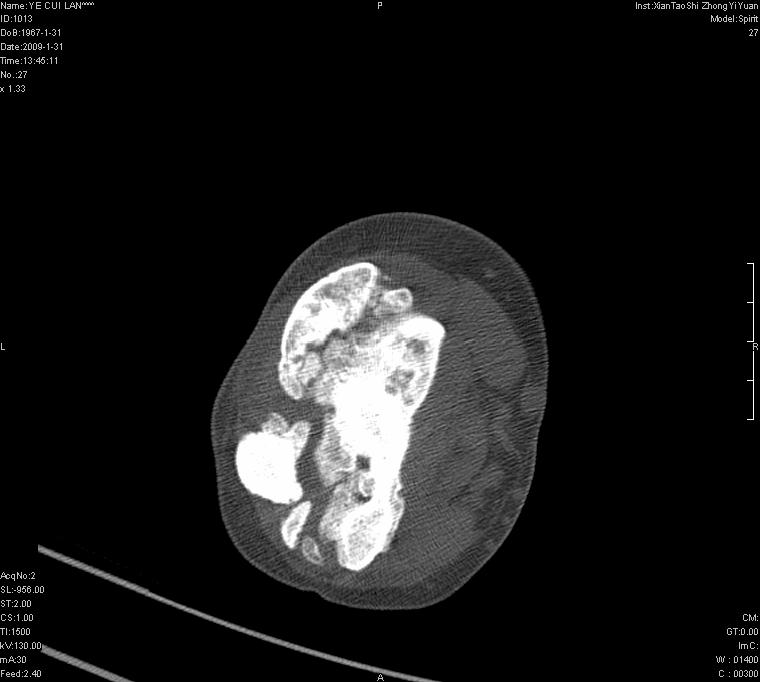

以下是引用王明发在2009-2-9 11:53:00的发言:[br]支持夏科氏关节,必要时行脊髓mri检查 [br]夏科氏关节是指由于某些神经系统疾病引起的关节病变,也被称为神经性关节炎。常见病因有脊髓痨、脊髓空洞症等。原发的神经病变可以造成关节深部感觉障碍,对于关节的震荡、磨损、挤压、劳倦不能察觉因而也不能自主地保护和避免,而神经营养障碍又可使修复能力低下,使病人在无感觉状态下造成了关节软骨的磨损和破坏,关节囊和韧带松弛无力,易形成关节脱位和连枷关节。关节面的破坏和骨赘的脱落变成关节内游离体。关节外形饱满肿胀,内有出血和渗出。这种病早期并无疼痛,不易被病人重视,仅表现为关节肿胀、无力、活动过度、动摇不稳。关节肿胀、无痛、活动范围超常是本病的重要特征。x光片可见有关节骨端广泛破坏、硬化或呈奇异形态,骨赘形成,关节间隙不规则或增宽,周围软组织钙化、关节内游离体、骨碎片等。结合x光片及临床症状,病人又有神经系统原发病症,即可确诊

以下是引用hhcckk在2009-2-9 14:31:00的发言:[br]夏科关节的六大表现[br]1.关节软组织肿胀。[br]2.关节的脱位与半脱位。[br]3.关节内的游离体。[br]4.关节面硬化,新骨形成。[br]5.骨质萎缩与破坏。[br]6.关节结构的紊乱。[br]加上患者无明显疼痛,诊断的把握性比较大